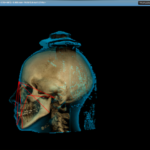

Valutazione delle caratteristiche scheletriche facciali mediante una metodica radiation free

L’interesse crescente per metodiche non invasive ha permesso lo sviluppo di nuovi strumenti di imaging che potrebbero migliorare il ruolo dei tessuti molli nella diagnosi ortodontica.